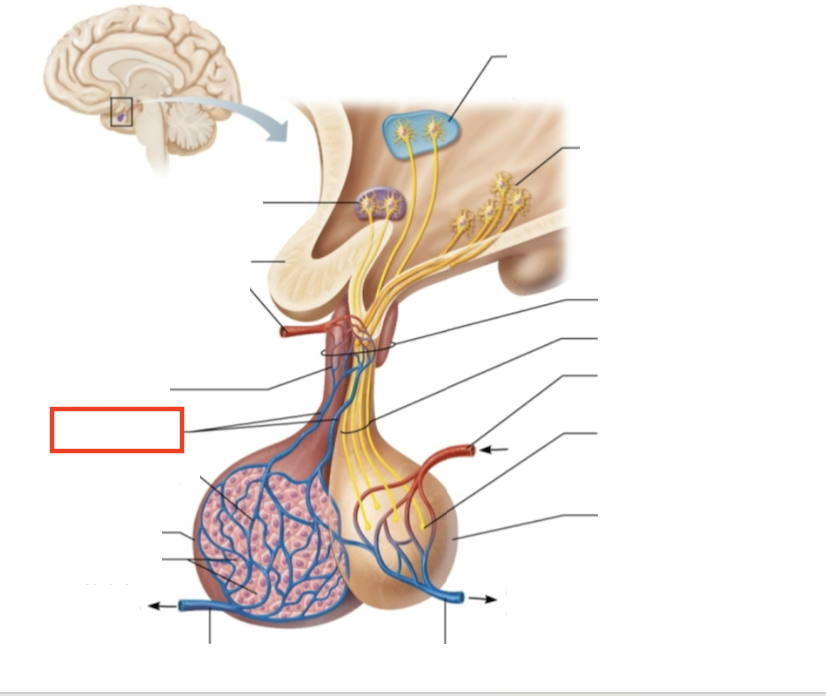

What structure is highlighted?

testes (male)

What structure is highlighted?

hypothalamic neurons in the paraventricular nuclei

What structure is highlighted?

neurons in the ventral hypothalamus

What structure is highlighted?

infundibulum (connecting stalk)

What structure is highlighted?

hypothalamic-hypophyseal tract

What structure is highlighted?

inferior hypophyseal artery

What structure is highlighted?

neurohypophysis (storage area for hypothalamic hormones)

What structure is highlighted?

posterior pituitary

What molecules are produced here?

oxytocin, ADH

What structure is highlighted?

venule

What structure is highlighted?

venule

What molecules are produced here?

TSH, FSH, LH, ACTH, GH, PRL

What structure is highlighted?

secretory cells of adenohypophysis

What structure is highlighted?

anterior pituitary

What structure is highlighted?

secondary capillary plexus

What structure is highlighted?

hypophyseal portal veins

What structure is highlighted?

primary capillary plexus

What structure is highlighted?

superior hypophyseal artery

What structure is highlighted?

superior hypophyseal artery

What structure is highlighted?

optic chiasma

What structure is highlighted?

hypothalamic neurons in the supraoptic nuclei